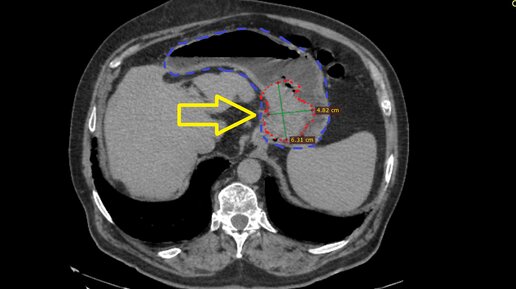

Крайне медленное течение рака желудка без лечения. Случай из практики

Онкология – это такая область медицины, в которой всегда есть место для невероятных случаев и ситуаций, вызывающих искреннее удивление даже у врачей, независимо от стажа работы в профессии. Сегодня я хотел бы поделиться очередным подобным случаем, который расширил границы моего представления о возможном. Многие слышали, наверное, что онкологические заболевания по-разному протекают у молодых и пожилых пациентов. У молодых пациентов обычно опухолевый процесс протекает более агрессивно, а у пожилых,...